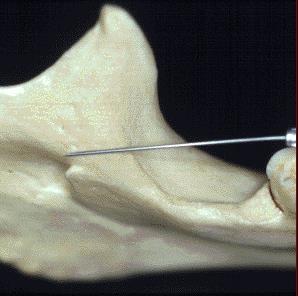

Es excavado Aspecto de una amplia hendidura, desarrolla una lengüeta ósea llamada espina de spix.

Situado a igual distancia de los bordes de las ramas en la prolongación de un plano imaginario que pasa por la superficie triturarte de los molaras inferiores

Longitud de 3 a 6 mm Orientación . Atrás, arriba y afuera limitando un ángulo de 45°

Ovalado de diámetro 2 a 5 mm

Borde anterior es cortante y falciforme. Borde posterior romo con suave declive con la cara externa del maxilar

Para realizar esta técnica existen dos formas una directa y otra indirecta.

Ambas tienen como referencia las siguientes estructuras anatómicas.

• Borde anterior del masetero

• Borde anterior del maxilar inferior

• Línea oblicua interna

• Línea oblicua externa

• Ligamento Pterigomaxilar o aponeurosis buccinatofaringea

• Trígono retro molar

• Caras oclusales de molares inferiores.

Orientación del bisel: menos crítico que con otro bloque de nervio, porque necesita aproximarse al nervio alveolar inferior y en un ángulo derecho .

• Procedimiento, asumir la posición correcta.

• Para bloquear el nervio alveolar derecho y un operador diestro, el sitio es a las 8 en punto con en posición contralateral del paciente.

• Para el bloque del nervio alveolar inferior izquierdo y operador diestro la posición es a las l0 en punto en posición contraria en la misma dirección del paciente.

• La posición supina del paciente ( se recomienda).